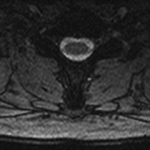

Figure 18B Figure 19A Figure 19B Figure 20

Truncation artifact Shading artifact Shading artifact Radiofrequency interference artifact

Truncation Artifact. (B) Corresponding axial MEDIC (multi-echo data image combination) MR image demonstrates normal appearance of the spinal cord.